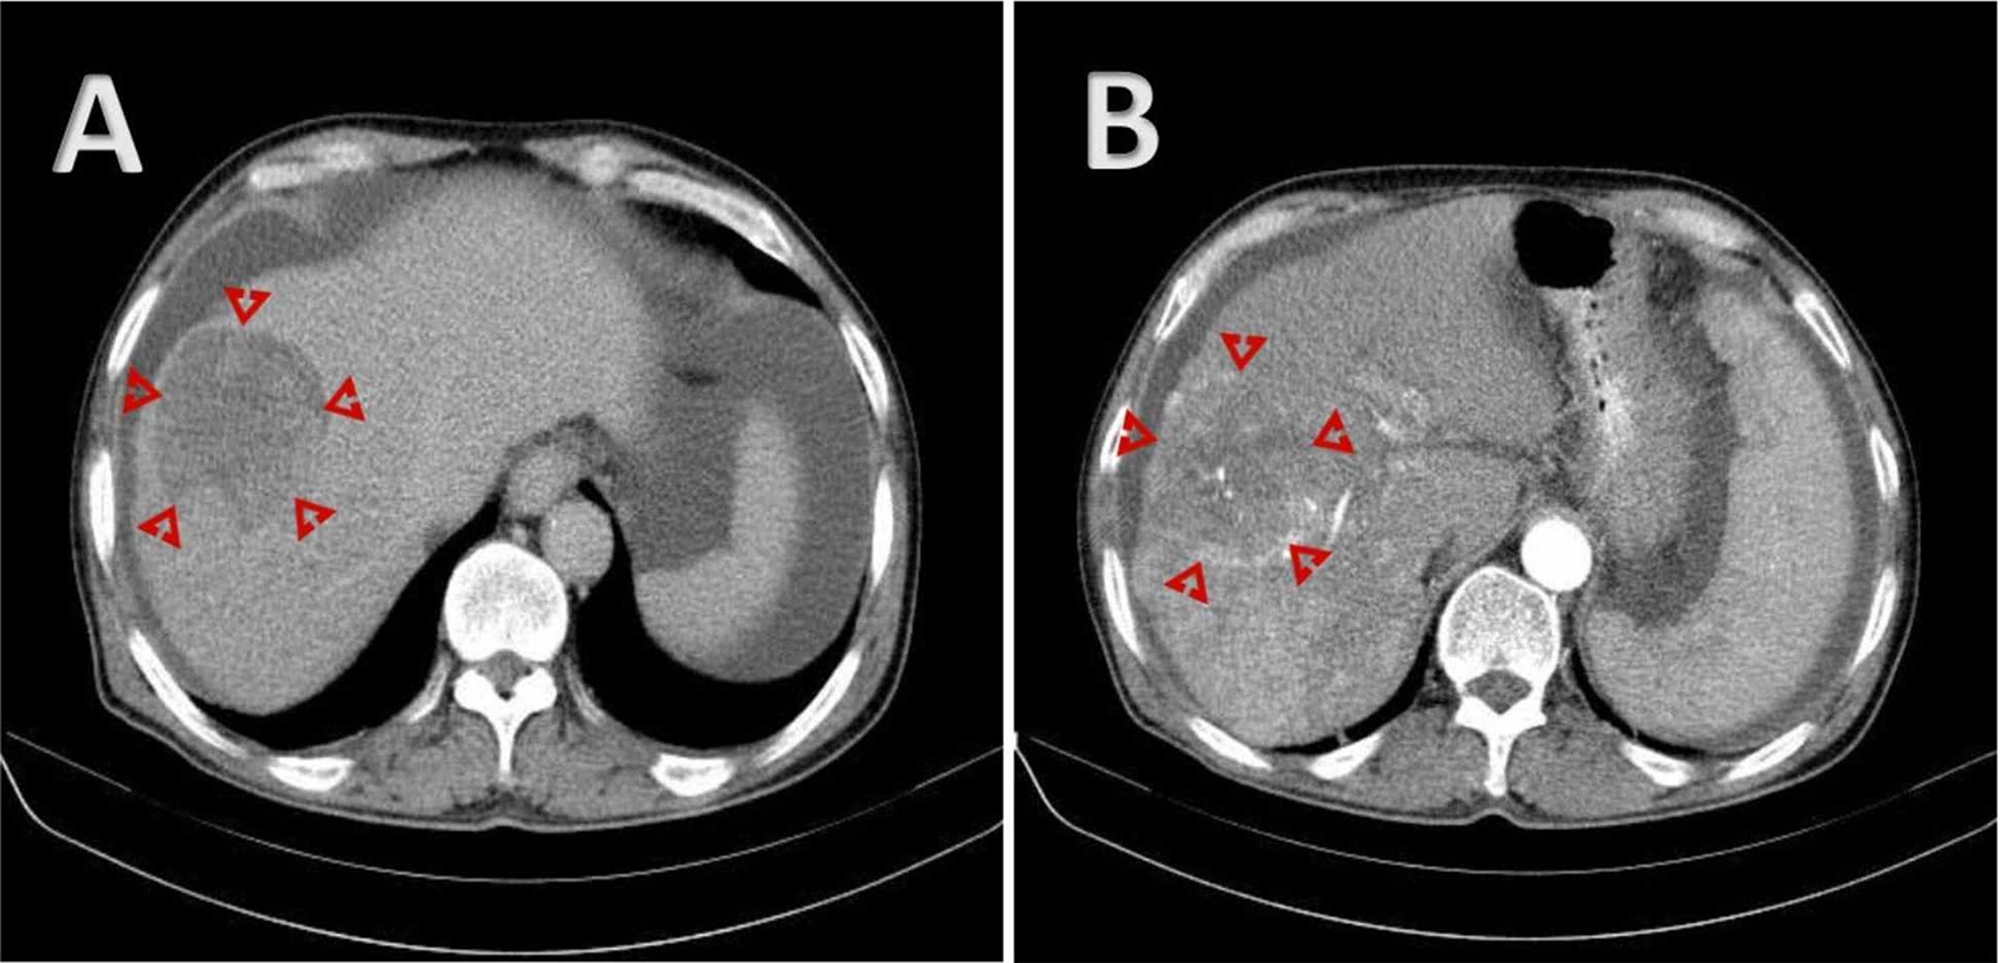

Surgical Treatment of Giant Cavernous Hepatic Haemangiomas Softball Size Tumor On Liver In the majority of patients, a proper diagnosis can be. This study is aimed to compare the size measurements of hepatocellular carcinoma (hcc) in three us imaging modalities, i.e. For example, smaller tumor size group patients were proportionally more likely. Staging looks at the size of the cancer (tumour) and whether it has spread anywhere else in the body. This. Softball Size Tumor On Liver.